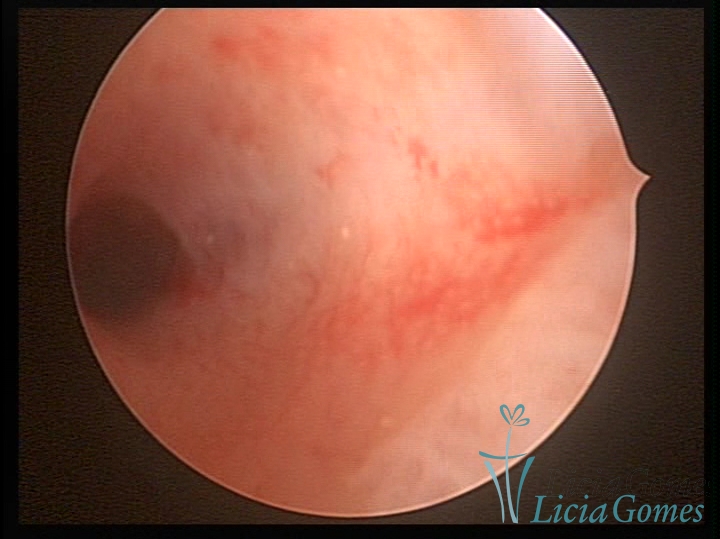

Bicornuate uterus

Malformation in which there is the lack of the flat portion of uterine fundus due to the lack of fusion on the proximal portion of paramesonephric ducts. The uterine fundus has two narrowed spaces in a divergent oblique angulation. It may be complete, from the fundus to the cervix; or partial, completely dividing the uterine cavity.

The tilted uterus which presents the most difficult hysteroscopic diagnosis occurs when there is only a small indentation of the uterine fundus.